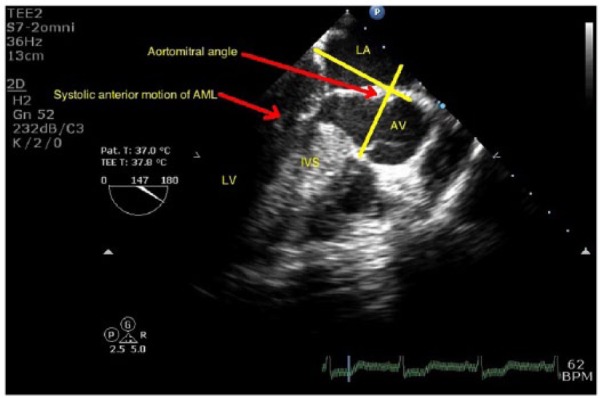

Predisposing factors that cause SAM are (1) excessive anterior or posterior leaflet tissue; (2) any anatomical or surgical translocation of the mitral valve anteriorly; (3) aortomitral angle <120° (Figure 1; Supplementary Clip 1); (4) pathological or post-surgical correction elongation of the anterior leaflet; (5) annular undersizing in mitral valve repair; (6) chordal anomalies such as elongation and buckling; (7) surgical chordal interventions such as transection, translocation, and reimplantation; (8) anterior and medial displacement of the papillary muscles; (9) bulging subaortic septum; (10) absolute height of the posterior leaflet (>1.5 cm); (11) anterior to posterior leaflet height ratio (<1.4); and (12) minimum distance from the coaptation point to the septum (C-Sept, <2.5 cm).2

Figure 1.

Transesophageal echocardiography midesophageal long-axis view showing systolic anterior motion of anterior mitral leaflet, bulging of interventricular septum, and aortomitral angle. AV indicates atrioventricular; IVS, interventricular septum; LA, left atrium.